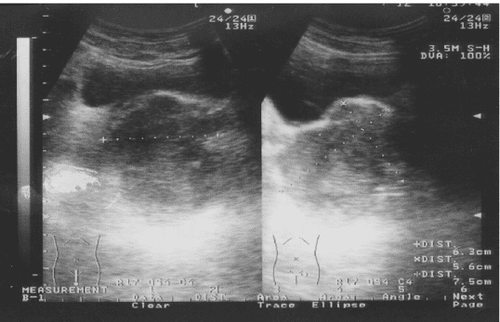

• Chụp CT hoặc chụp cộng hưởng từ (MRI) vị trí u;

Thông qua hình ảnh thu được sau khi chụp CT, các bác sĩ sẽ đánh giá kích thước khối u cơ vân ác tính ở trẻ em. Đối với các tổn thương ở đầu và cổ sẽ thường được xác định tốt hơn với chụp cộng hưởng từ (MRI). Dựa vào sinh thiết hoặc cắt bỏ khối u để chẩn đoán xác định bệnh sarcoma cơ vân.

Để xét nghiệm đánh giá di căn, bệnh nhân sẽ chụp CT vùng ngực, chụp hệ xương, chọc hút tủy xương 2 bên và thực hiện sinh thiết tủy xương.